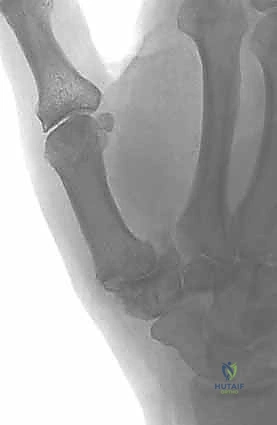

التصوير بالأشعة السينية (X-rays):

تُعد الأشعة السينية الأداة المعيارية الذهبية لتأكيد التشخيص وتحديد مرحلة المرض. يطلب الدكتور هطيف وضعيات تصوير محددة (مثل وضعية روبرت - Robert's View) لرؤية المفصل بوضوح. تُظهر الأشعة:- تضيق المسافة بين العظم المربعي وعظم المشط الأول (دليل على فقدان الغضروف).

- النتوءات العظمية (الزوائد العظمية).

- التصلب تحت الغضروفي (زيادة كثافة العظم نتيجة الاحتكاك).

- درجة انزلاق المفصل.

يستخدم الدكتور هطيف تصنيف إيتون-ليتلر (Eaton-Littler Classification) العالمي لتصنيف شدة الخشونة من المرحلة الأولى (I) إلى المرحلة الرابعة (IV)، وبناءً عليه يتم تحديد خطة العلاج الأنسب.